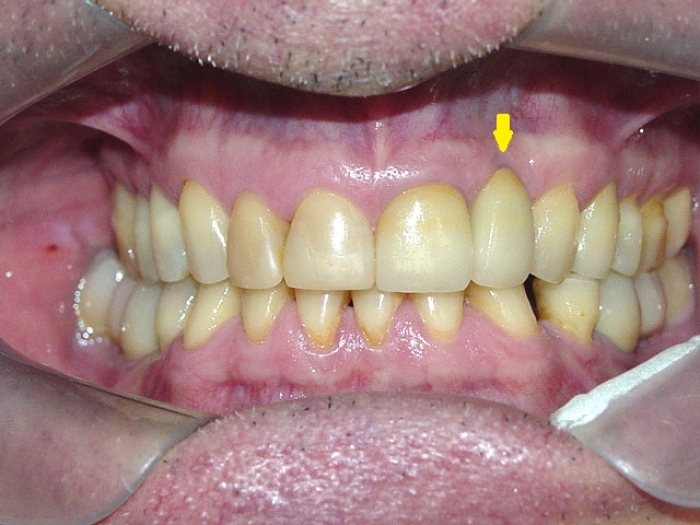

Imagens iniciais, mostrando ausência do elemento 22

Imagem inicial